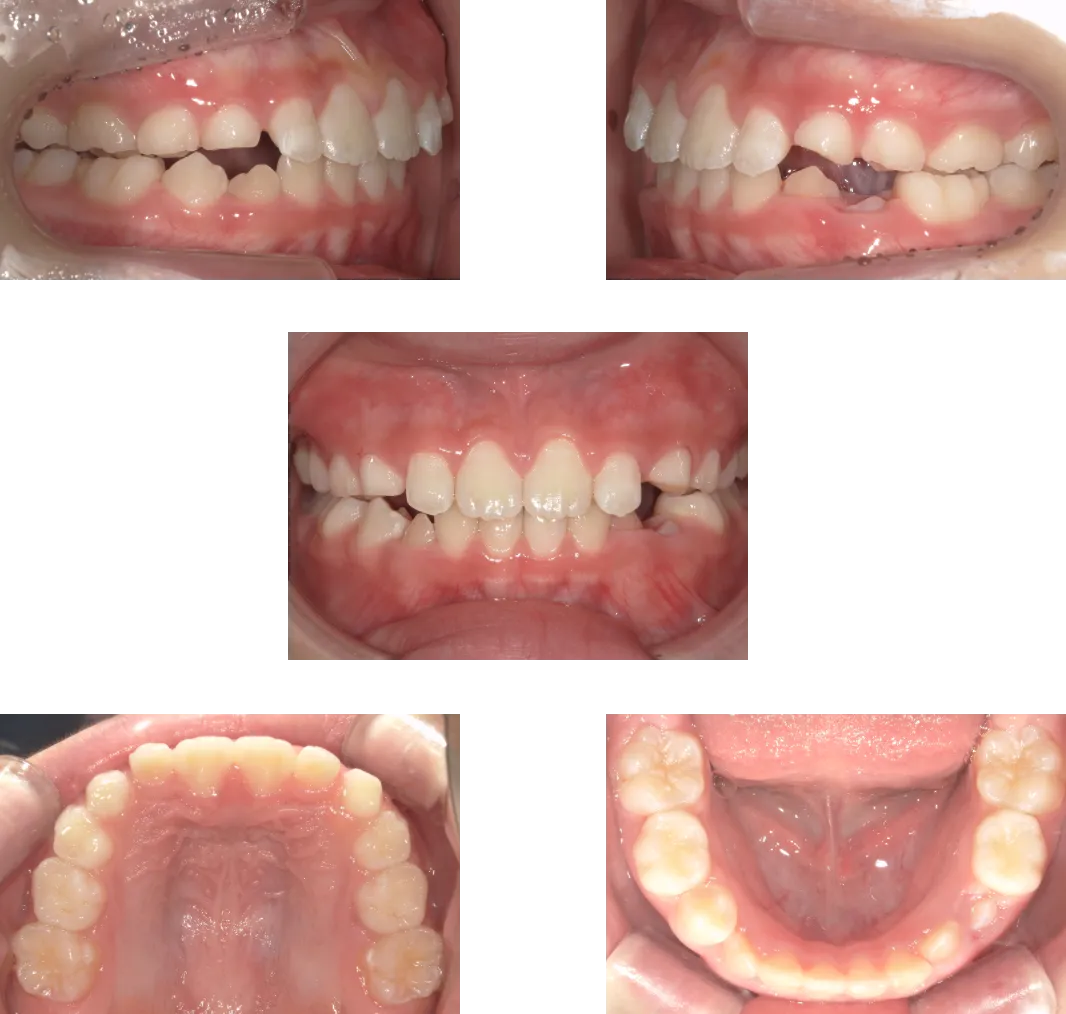

上顎前突 -7歳-

• Before

• After

診断

過蓋咬合を伴う重度骨格性上顎前突

治療期間

2年

抜歯

なし

料金

600,000+550,000円(調整料を含む。2期開始時分析料別途発生)

リスク

痛み、軽度の歯根吸収、術後の変化